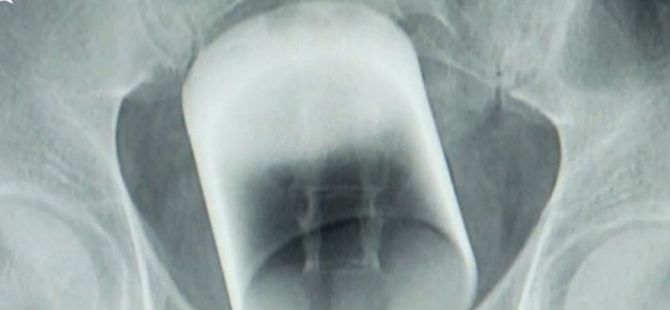

07 Eylül 2017 Perşembe 20:38Çin'de hastaneye çığlıklar içinde gelen adamın röntgenini çeken doktorlar adeta şok yaşadı. Doktorlar genç adamın anüsünde 7 santimetre çapında bir cam bardak buldu. Kırılmamış vaziyette bulunan bardağın nasıl girdiği ise henüz çözülemedi.

Çin’de hafta başında hastaneye kaldırılan bir genç adam çığlıklar içinde ortalığı velveleye verince herkes şaşırmıştı. Kalçasında bir ağrı olduğunu söyleyen ve doktorlardan yardım isteyen evli ve genç adam neredeyse bayılacak gibi olunca doktorlar müdahale ederek röntgen çektirdi.